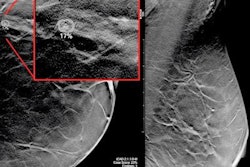

New technologies are dramatically changing how breast imaging services are delivered in 2020. Digital breast tomosynthesis, artificial intelligence, abbreviated MRI, and other technologies are giving breast imaging specialists new tools in their fight against breast cancer -- and the latest research indicates they may be winning.